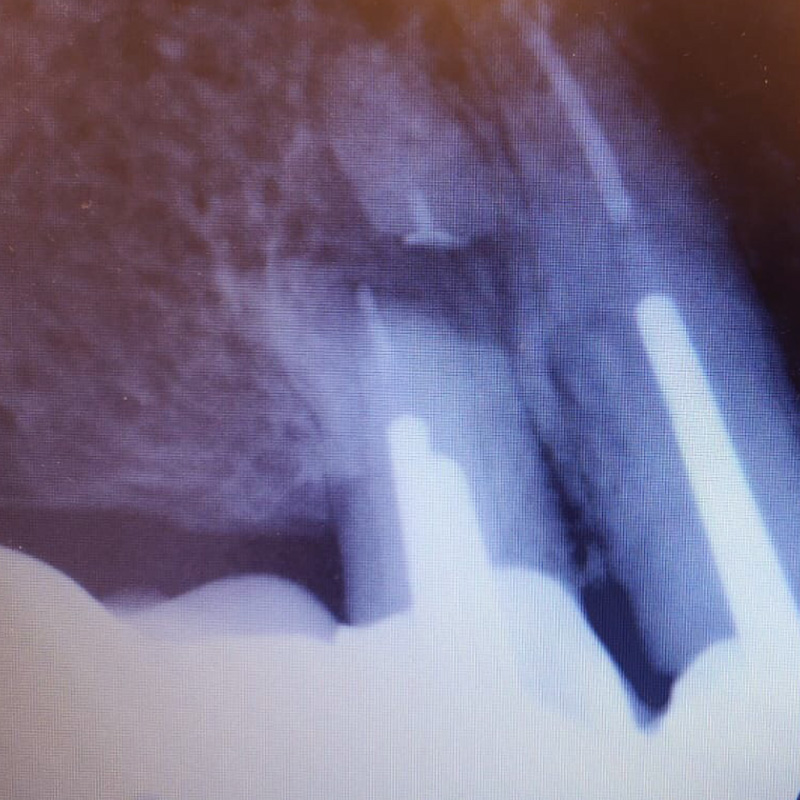

В нашу клинику обратился пациент с жалобами на резкую боль при накусывании справа вверху в области мостовидного протеза, который был установлен в другом лечебном учреждении.

После анализа сделанной рентгенограммы, врач-хирург Тарасов Денис Геннадьевич провёл резекцию верхушки корня зуба 1.4.

При неэффективности терапевтического лечения путём резекции верхушки корня одновременно с частью корня отсекается очаг воспаления в канале.